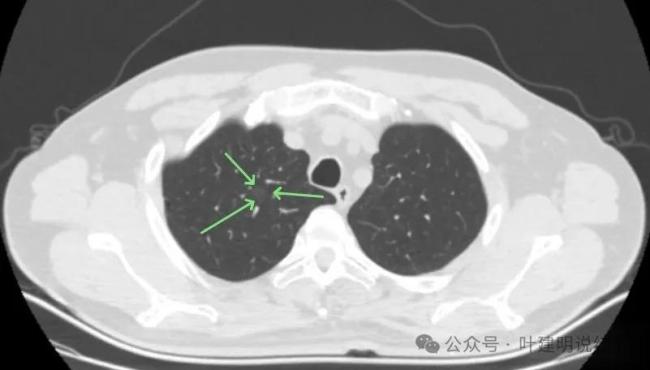

32歲兒子陪護69歲母親雙雙確診肺癌 早篩挽救生命!69歲的陳阿姨在一次社區(qū)免費體檢中查出肺癌,腫瘤尚未擴散,手術(shù)順利。32歲的兒子小李在醫(yī)院陪護期間,目睹母親術(shù)后恢復(fù)良好,主動要求做一次胸部CT檢查,結(jié)果發(fā)現(xiàn)肺部有一枚12毫米的磨玻璃結(jié)節(jié)。幾個月后復(fù)查,結(jié)節(jié)未消退且形態(tài)更明顯,最終通過手術(shù)確診為早早期腺癌。幸運的是,發(fā)現(xiàn)及時,術(shù)后無需化療,只需定期隨訪。

為何選擇低劑量CT而非胸片或腫瘤標志物?答案在于“敏感度”。胸片對小于1厘米的肺結(jié)節(jié)漏診率高達60%以上,而低劑量CT能清晰捕捉到幾毫米的磨玻璃結(jié)節(jié)。腫瘤標志物則在早期肺癌中多無異常,無法用于篩查。目前,國際和中國指南均唯一推薦低劑量CT作為肺癌篩查工具,其有效性已被美國國家肺癌篩查試驗(NLST)證實:連續(xù)三年篩查可使肺癌死亡率降低20%。對于像小李這樣發(fā)現(xiàn)12毫米磨玻璃結(jié)節(jié)的患者,臨床處理有明確路徑。中國《肺結(jié)節(jié)診治專家共識(2024版)》建議,直徑大于10毫米的純磨玻璃結(jié)節(jié),若持續(xù)存在,應(yīng)每6個月復(fù)查一次高分辨率薄層CT。若結(jié)節(jié)增大超過2毫米、出現(xiàn)實性成分,或有毛刺、血管穿行等惡性征象,即應(yīng)考慮手術(shù)。小李的結(jié)節(jié)在復(fù)查中未消退且更明顯,符合手術(shù)指征,最終通過微創(chuàng)肺段切除,病理確診為早早期腺癌,術(shù)后無需進一步治療。